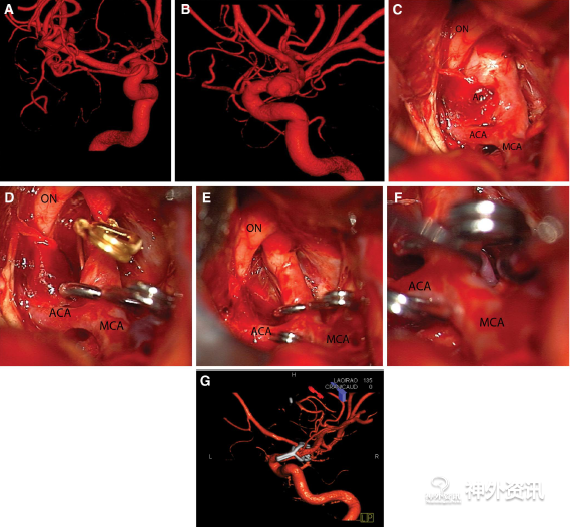

图2. A、B. 右侧颈内动脉DSA前后位和内侧斜位3D血管重建提示,颈内动脉床突上段背侧宽基底BBA,指向背内侧;C. 术中照片显示,右侧颈内动脉床突上段背侧宽基底BBA,于视神经下方,瘤顶被血栓覆盖;D. 临时阻断夹控制近端,再使用45°窗式夹夹闭;F.在颈内动脉末端后部、脉络膜前动脉下方,使用弯夹紧贴窗式夹夹闭瘤颈远端;G. 术后3D血管重建提示,窗式夹跨越颈内动脉远端夹闭动脉瘤。